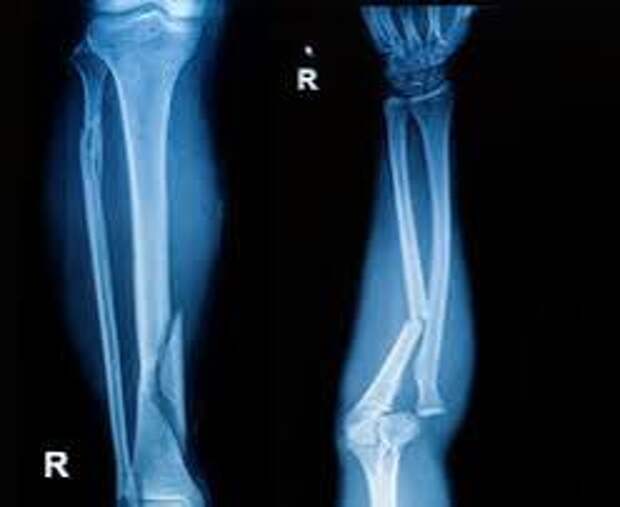

Ударно-волновая терапия (УВТ) представляет собой инновационный способ лечения замедленного заживления перелома костей после операции остеосинтеза. Методика основана на воздействии акустических волн низкой интенсивности, что способствует улучшению микроциркуляции крови, активизации обменных процессов и стимуляции регенерации костной ткани.